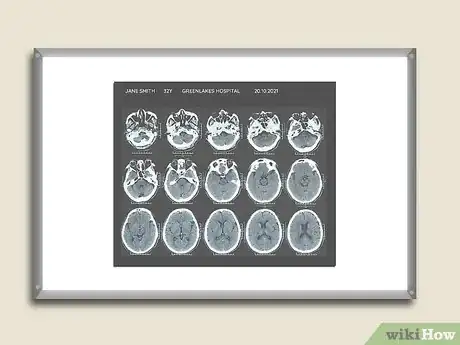

1Read the information on the CT scan. Check to see what is printed on the films to determine they are yours and what part of the body is represented in the films.

- You should see your name and other identifying information like your birthdate. The name of the hospital or medical facility where the films were taken and the date the study was performed should be printed on each film. You do not want to look at someone else’s films and become upset if you see an abnormality.

- Your expectations about what you will see are determined by what part of your body was studied. The CT of your brain will be compact with your brain encased inside the thin bone of your skull. The CT of your leg or arm will be compact but it will have length; the scan will have images of your bones and the surrounding soft tissue (muscle and fat). The CT of your abdomen will be large and very complex because you will be seeing things like your small intestines curled up like a snake right next to your kidneys, liver, spleen, etc.